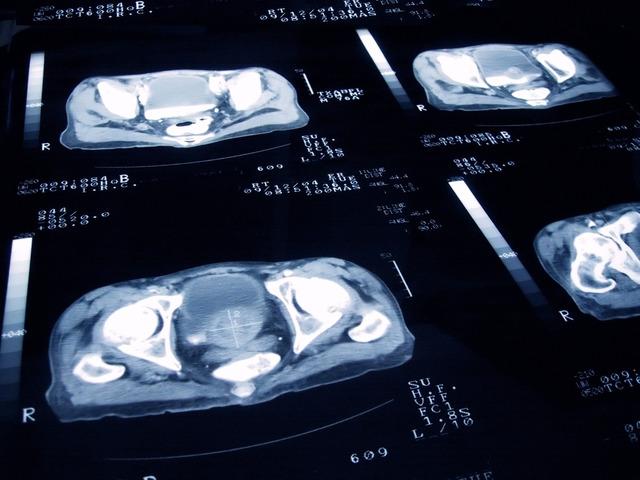

Prostat sağlığı konusunda endişe duyanların mutlaka bir uzmana başvurması gerektiğini vurgulayan Opr. Dr. Kıvrak, şunları söyledi: “Kendinize teşhis koymaktan veya internetteki kanıtlanmamış bilgilere göre hareket etmekten kaçının. PSA seviyenizi düzenli olarak kontrol edin. Bu test prostat kanserinin erken teşhisinde önemli rol oynuyor.